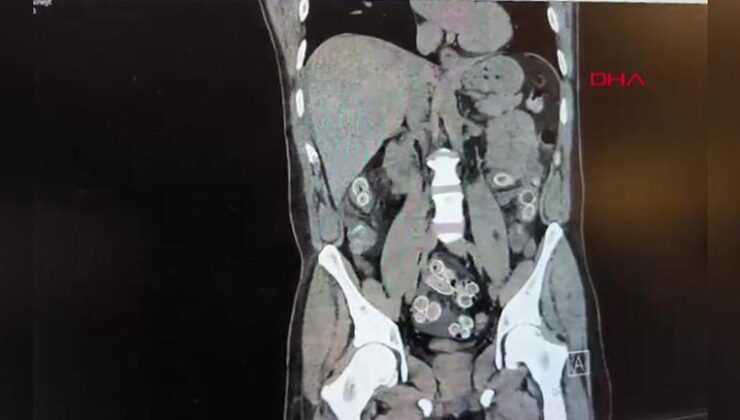

Fas’tan uçakla Türkiye’ye gelen bir kişi, mide ağrısı şikayetiyle özel hastaneye gitti. Şüphelinin mide ve bağırsaklarında uyuşturucu madde tespit edildi.

Hastane yetkilileri durumu polise ekiplerine bildirdi. Hızla ameliyata alınan şüphelinin midesinden 49 adet paketlenmiş, toplam 259 gram ağırlığında uyuşturucu madde çıkarıldı.